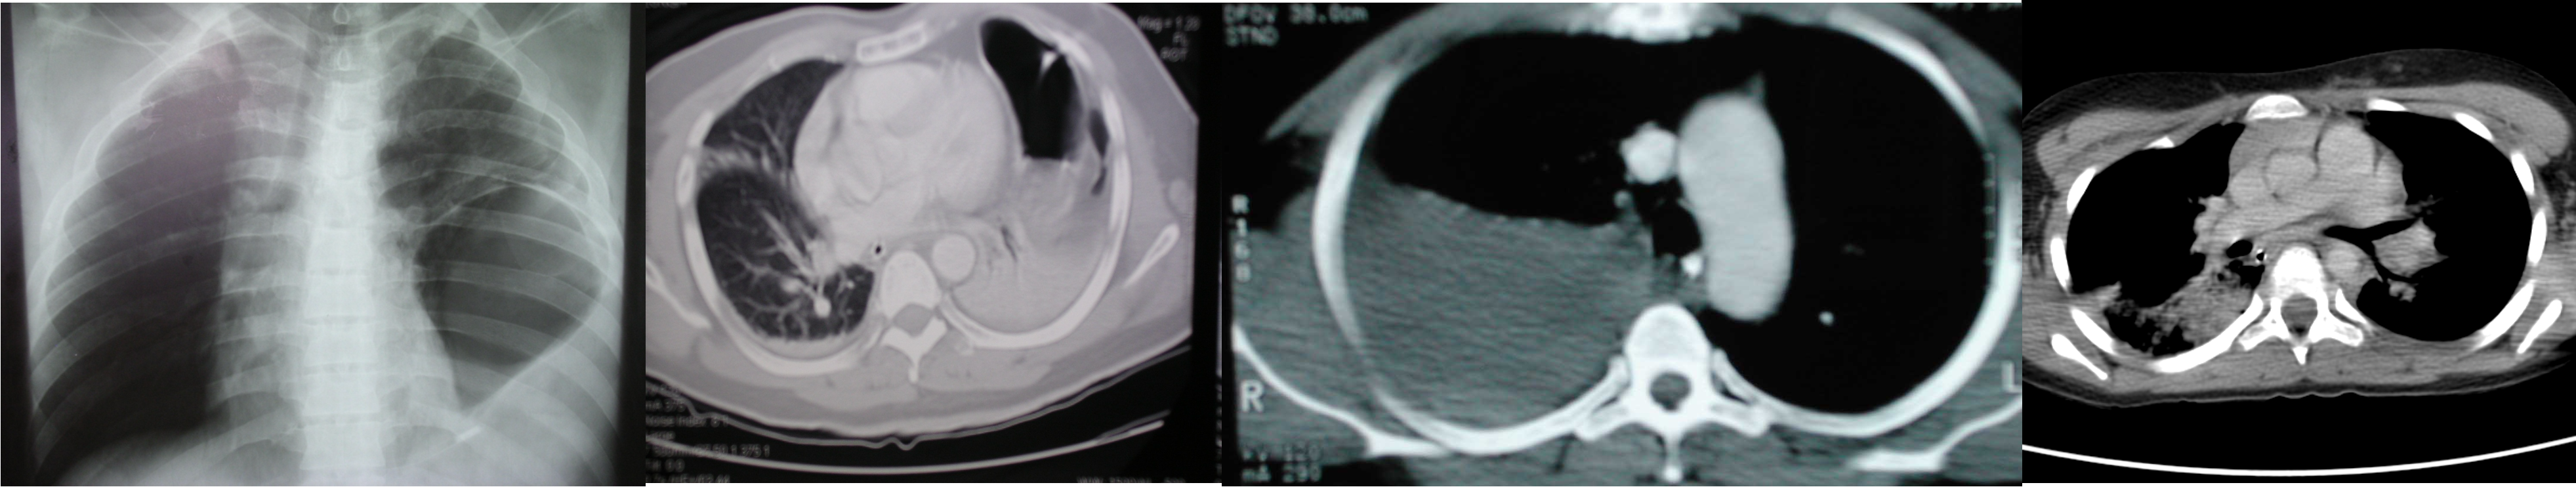

Thoracic injury

Diagnostic modalities:

CXR, ultrasonography, chest CT, esophagography, esophagoscopy, bronchoscopy, and angiography